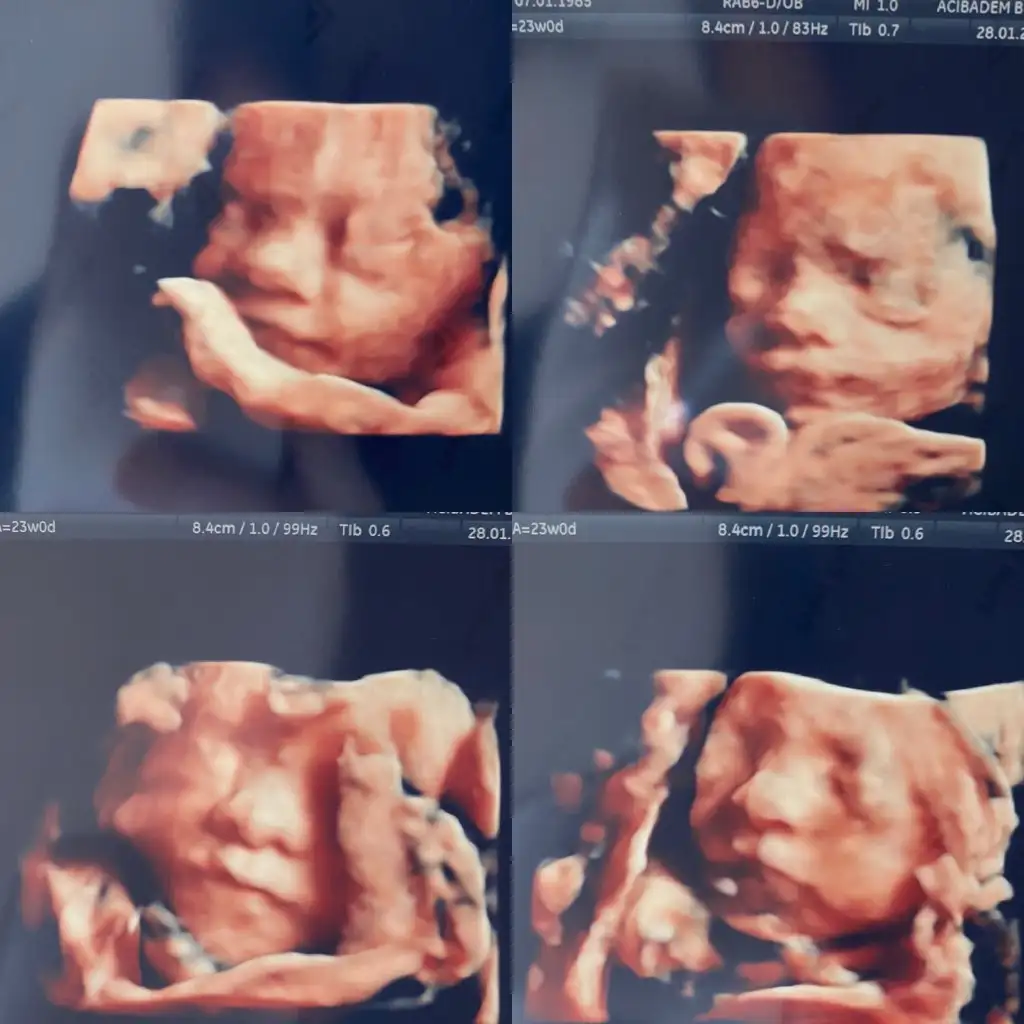

Bebis 600 gr olmus kizlar. Kasilmami bu sefer ultrasonda gormedi cok sukur. Ama tarif ettiklerime gore evde oldugunu soyledi. Enfeksiyon var mi diye bi bakalim once yoksa nidilat diye bi ilac varmis tansiyon ilaciymis ama kadin dogumcular cok kullaniyormus. Erken dogumu engellemek icin veriliyoms bu ilac. Enfeksiyon yoksa bu ilaca baslicam.